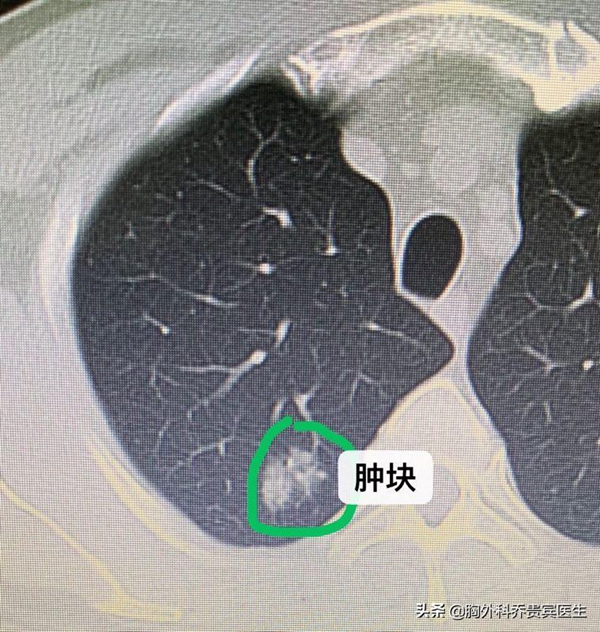

最近入院的陈大哥,把大家都吓了一跳。陈大哥咳嗽了一段时间,继而去医院检查,发现肺部有一个肿块。继续全家都很惊慌,坚持要手术。

51岁的陈大哥最近一直咳嗽不好,学医的儿子很敏感,劝他去做一个肺部CT。检查出来,发现陈大哥的右上肺有一个结节。

陈大哥学医的儿子,看到这个结果,坚决要求尽快手术。我看了片子,觉得这个结节看起来不能完全排除肿瘤,但也不能完全排除是良性的疾病。

由于家属比较坚持,我们考虑到这个结节位置靠肺的外周,可以做一个非常小的楔形切除就可以达到诊断和治疗的目的,因此,近日我们为陈大哥进行了单孔胸腔镜下的微创切除手术,术中冰冻回报是隐球菌感染。